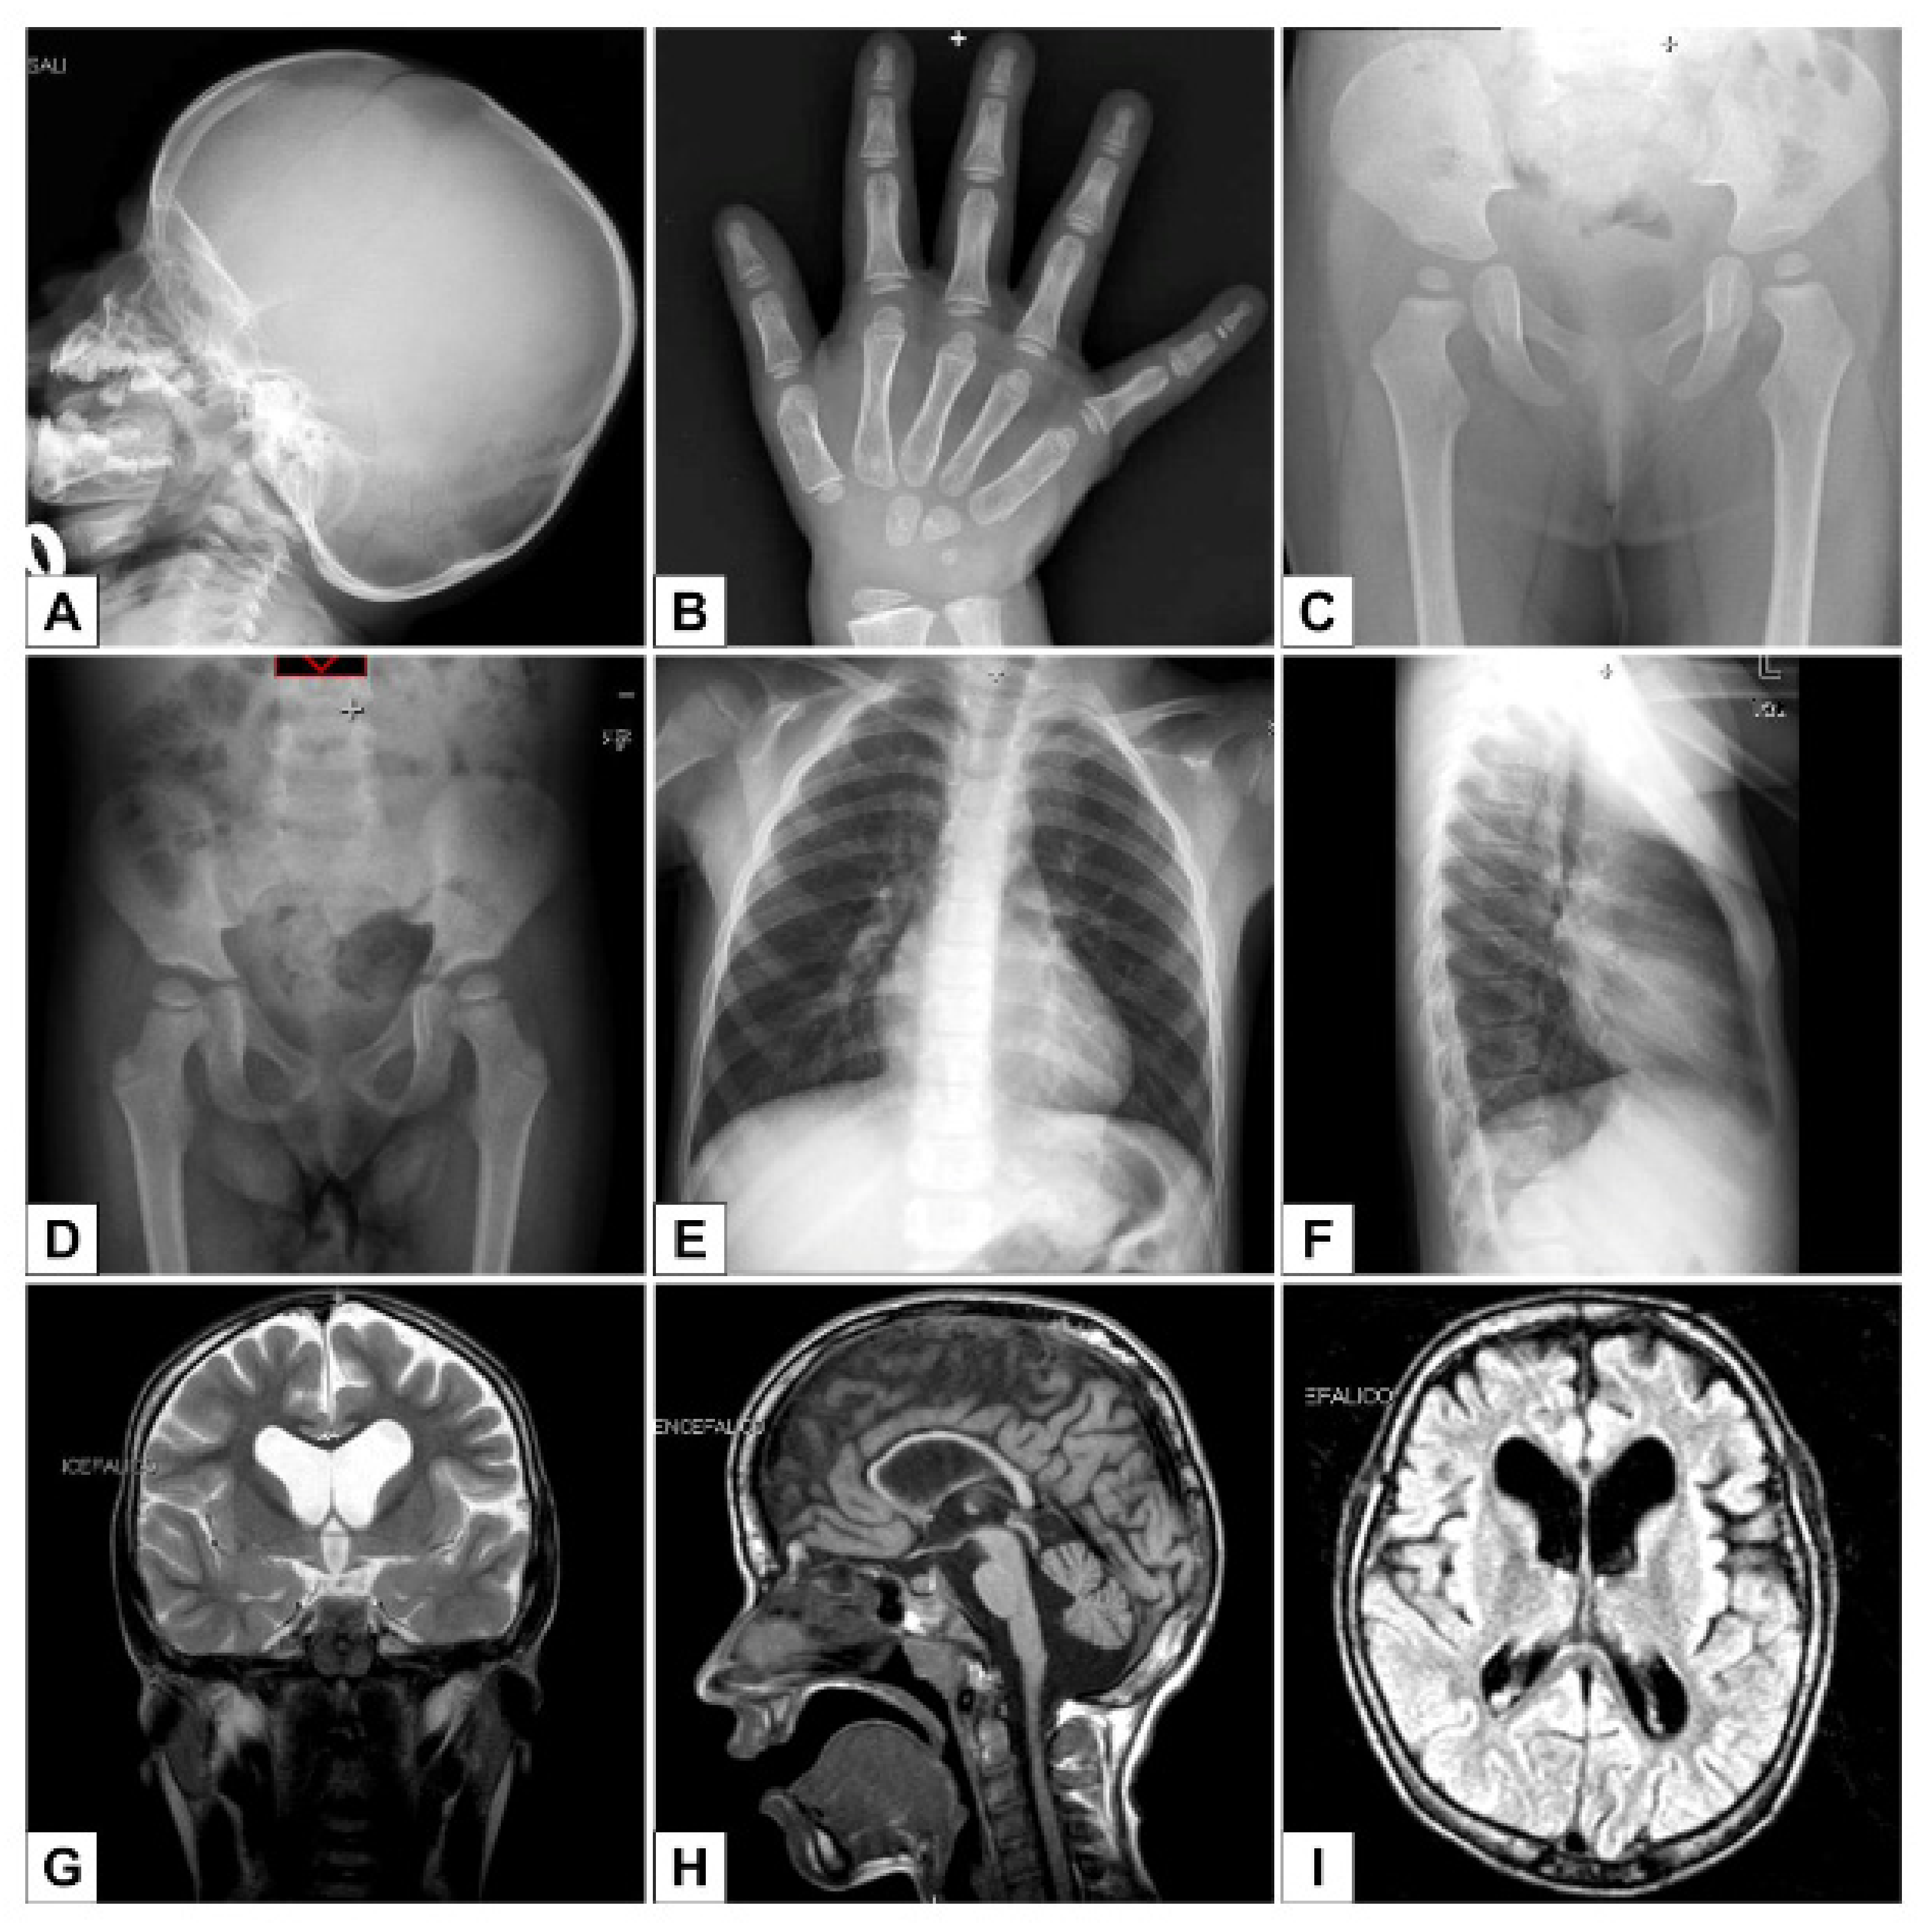

Clinical Manifestations in a Girl with NAA10-Related Syndrome and Genotype–Phenotype Correlation in Females

Maini, I.; Caraffi, S.G.; Peluso, F.; Valeri, L.; Nicoli, D.; Laurie, S.; Baldo, C.; Zuffardi, O.; Garavelli, L. Clinical Manifestations in a Girl with NAA10-Related Syndrome and Genotype–Phenotype Correlation in Females. Genes 2021, 12, 900. https://doi.org/10.3390/genes12060900